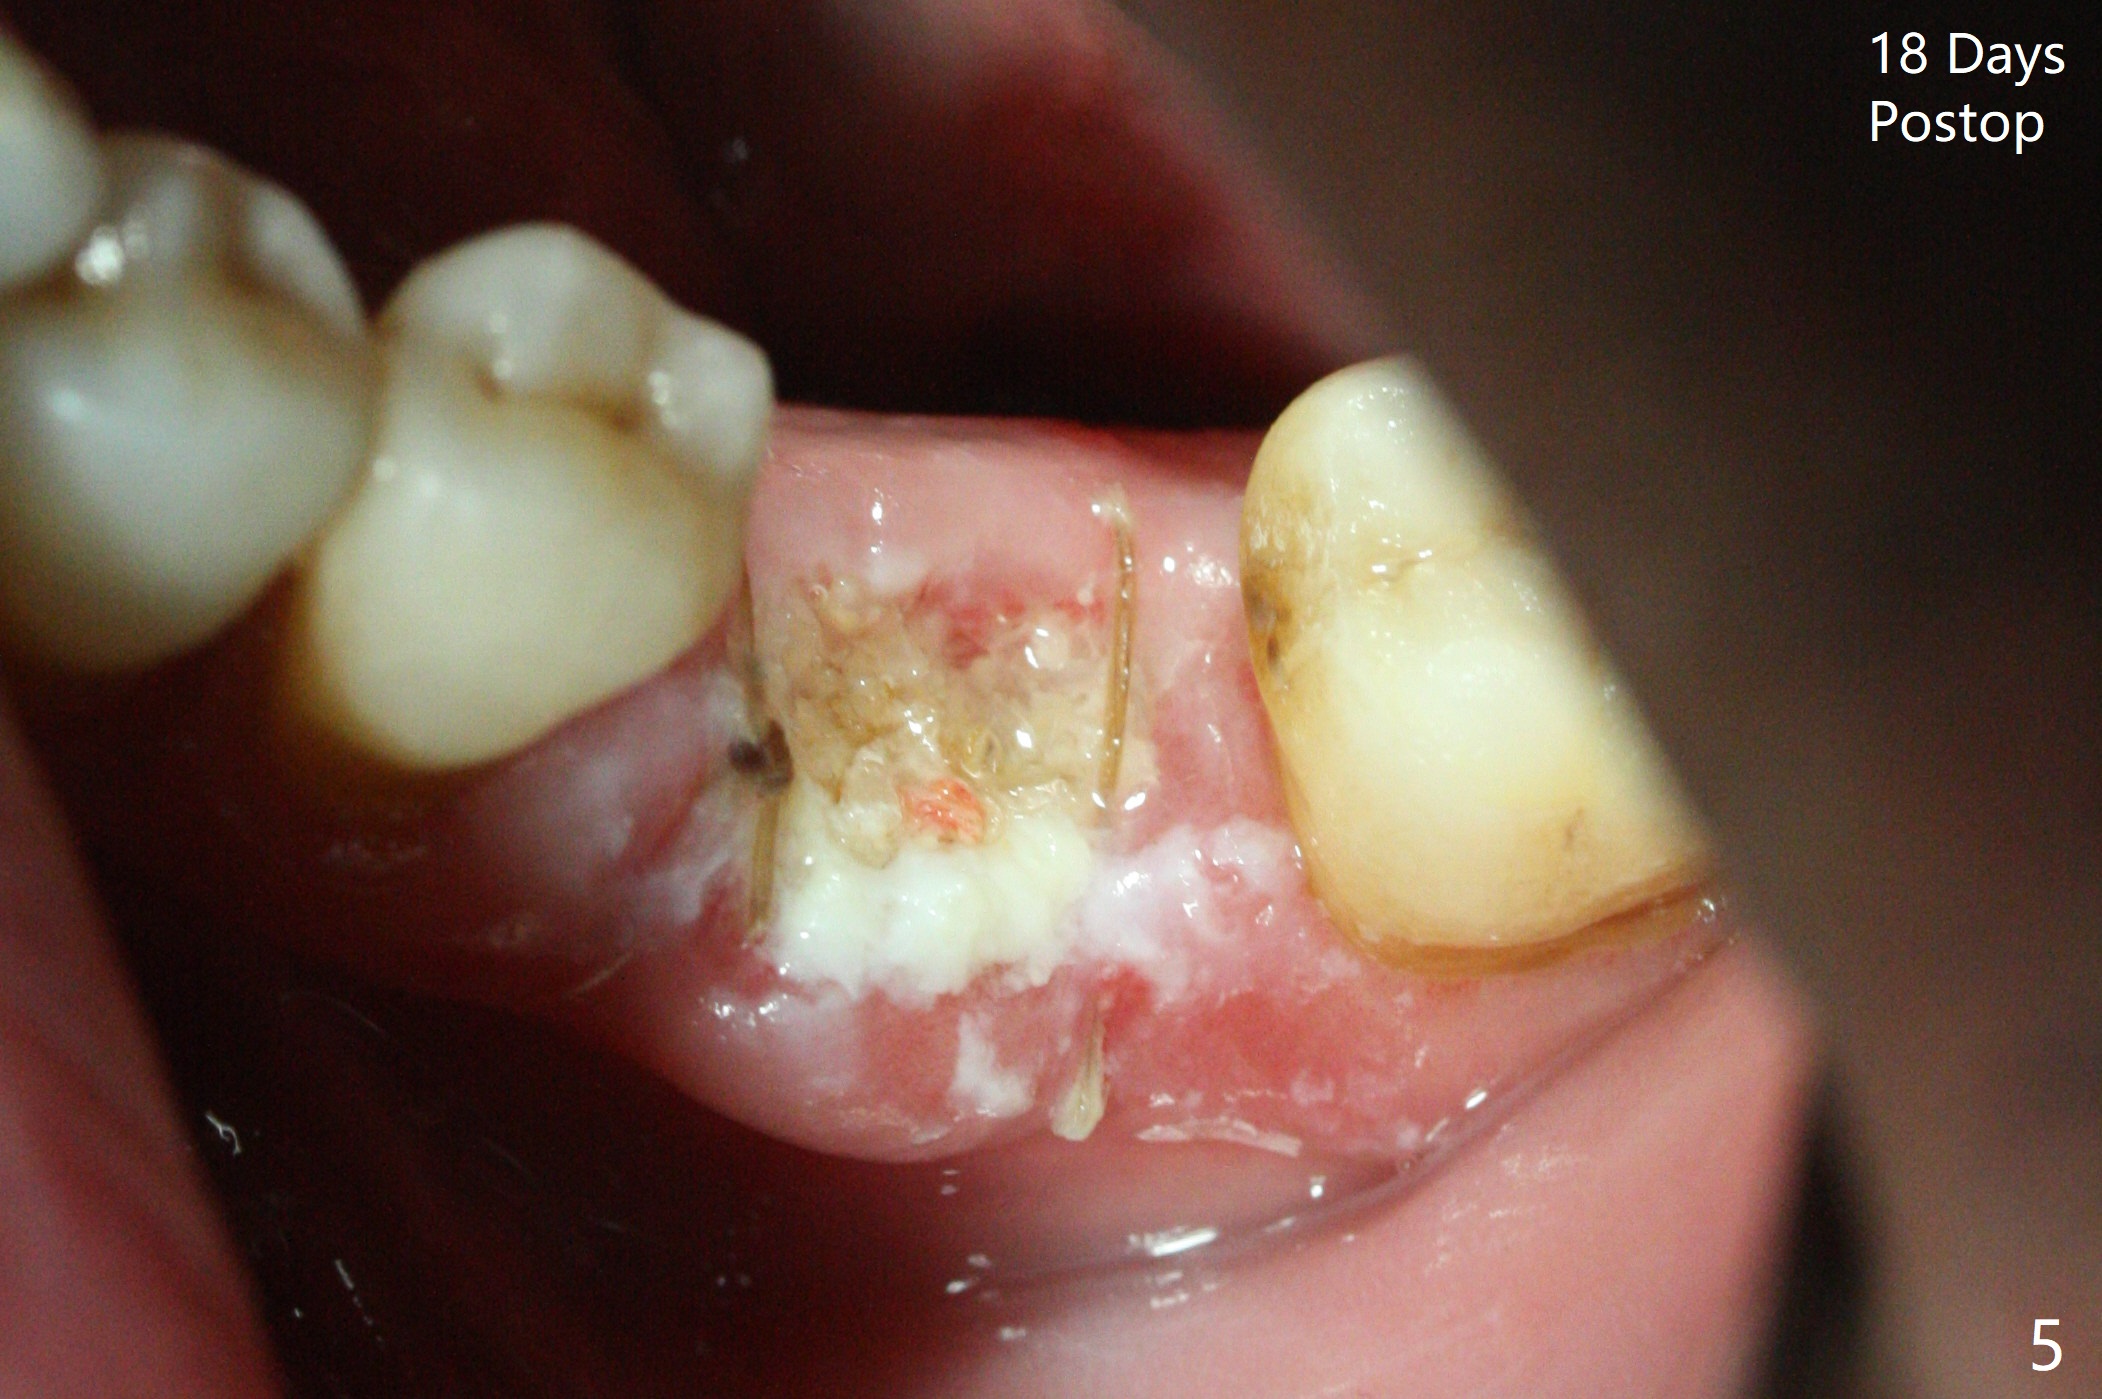

Extraction of the tooth #19 with large PARL (Fig.1,2) confirms the loss of buccal plate, but the crestal bone exists. After failure to place an implant in the middle socket with removal of the lingual septal bone, socket preservation is done with PRF and sticky bone (Fig.3). There is possibility to place a ~4 mm implant in the mesial socket (Fig.4). Or just drop a 5x11 mm Bicon Implant into the large socket, surrounded by sticky bone. When periodontal dressing is removed 18 days postop, the bone graft seems to remain to be "sticky" yellowish, while the granulation tissue has started to grow into the center of the socket from the previously buccal and lingual furcae (Fig.5 reddish). Granulation tissue seems to cover the bone graft (Fig.6), although there is smells when the periodontal dressing is removed. Bone height reduces nearly 3 months postop (Fig.7). The buccal plate collapses (Fig.8), but there seems no further bone loss 4 months postop (Fig.9). Because of buccal plate loss, an implant will be placed lingually with guide (Fig.10-12 green). Bone graft may be placed buccally after implant placement with probing.